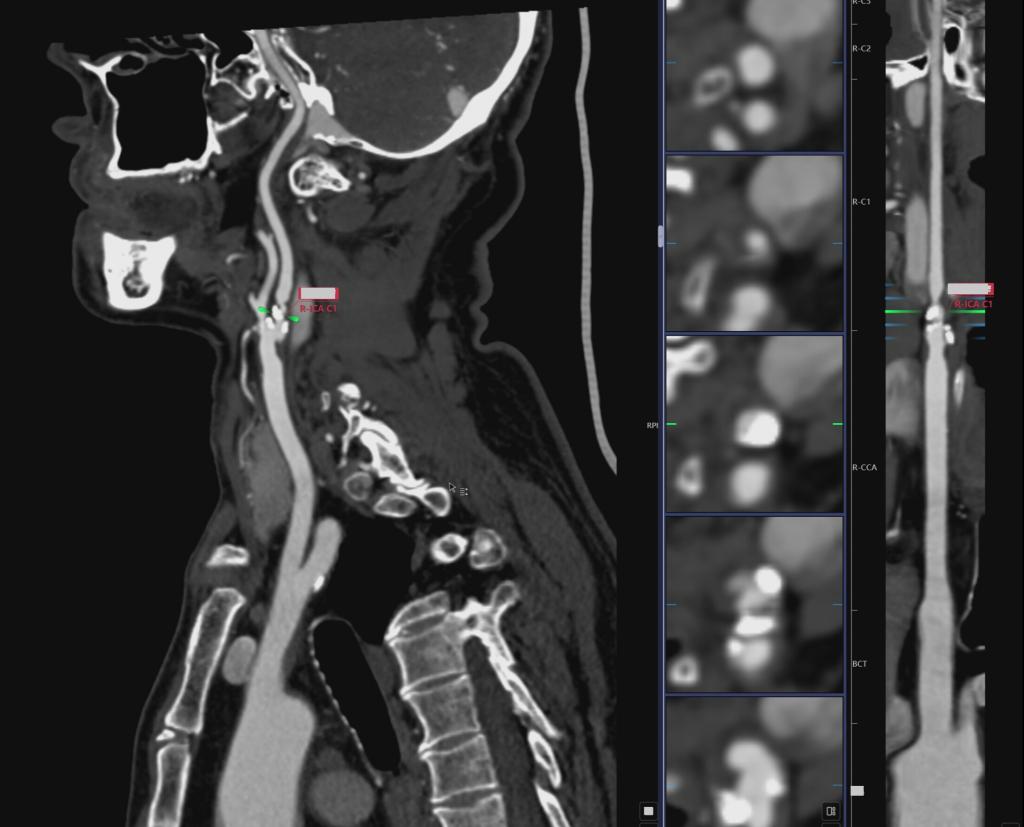

患者入院前,反复出现头晕、呕吐,并伴有黑朦、短暂性脑缺血发作(TIA)等症状。入院后颅脑MR检查显示“未见颅内新发梗死”,颈动脉B超提示右侧颈内动脉重度狭窄。初步诊断为右侧颈内动脉起始部重度狭窄、头晕、高血压病1级、腔隙性脑梗死。

经过全面术前评估和多学科协作诊疗(MDT)讨论,医疗团队认为患者症状与右侧颈动脉狭窄密切相关。由于颈动脉斑块质地硬、钙化明显,不适合行颈动脉支架术(CAS),在与家属充分沟通后,团队决定为患者实施右侧颈动脉剥脱术(CEA)。